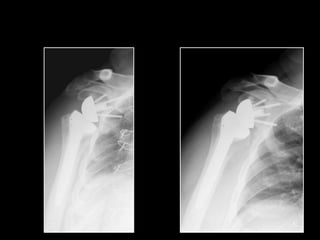

SURGICAL TECHNIQUE

MADRID